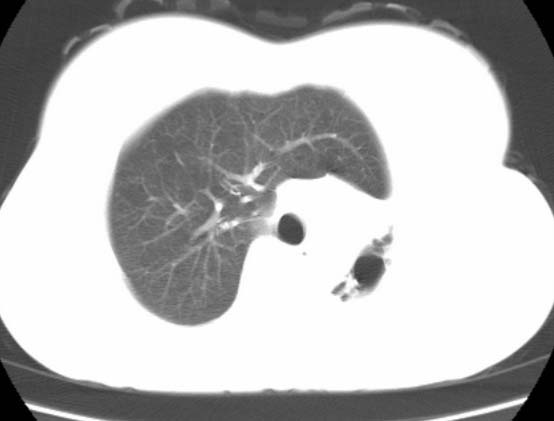

标题: CT25648:求教:是肺发育不全还是结核?

女  20岁。一月前咳血,诊“肺结核”抗痨治疗一月后,咳血停止,现复查。病人精神好。前后ct片对比未见明显变化。既往体检“正常”

1)考虑左肺结核并肺不张、支气管扩张。2)纵隔疝。

以前体检正常只能考虑左肺结核并肺不张、支气管扩张。2)纵隔疝。

考虑左肺结核,左肺毁损,纵膈左偏,既往体检正常不可靠,tb一个月也不会这个样子的,有钙化,应该病程较长,冰冻三尺非一日之寒!

左肺发育不全。

考虑左肺结核,左肺毁损,纵膈左偏,既往体检正常不可靠,tb一个月也不会这个样子的,有钙化,应该病程较长,冰冻三尺非一日之寒

结核,左肺毁损。